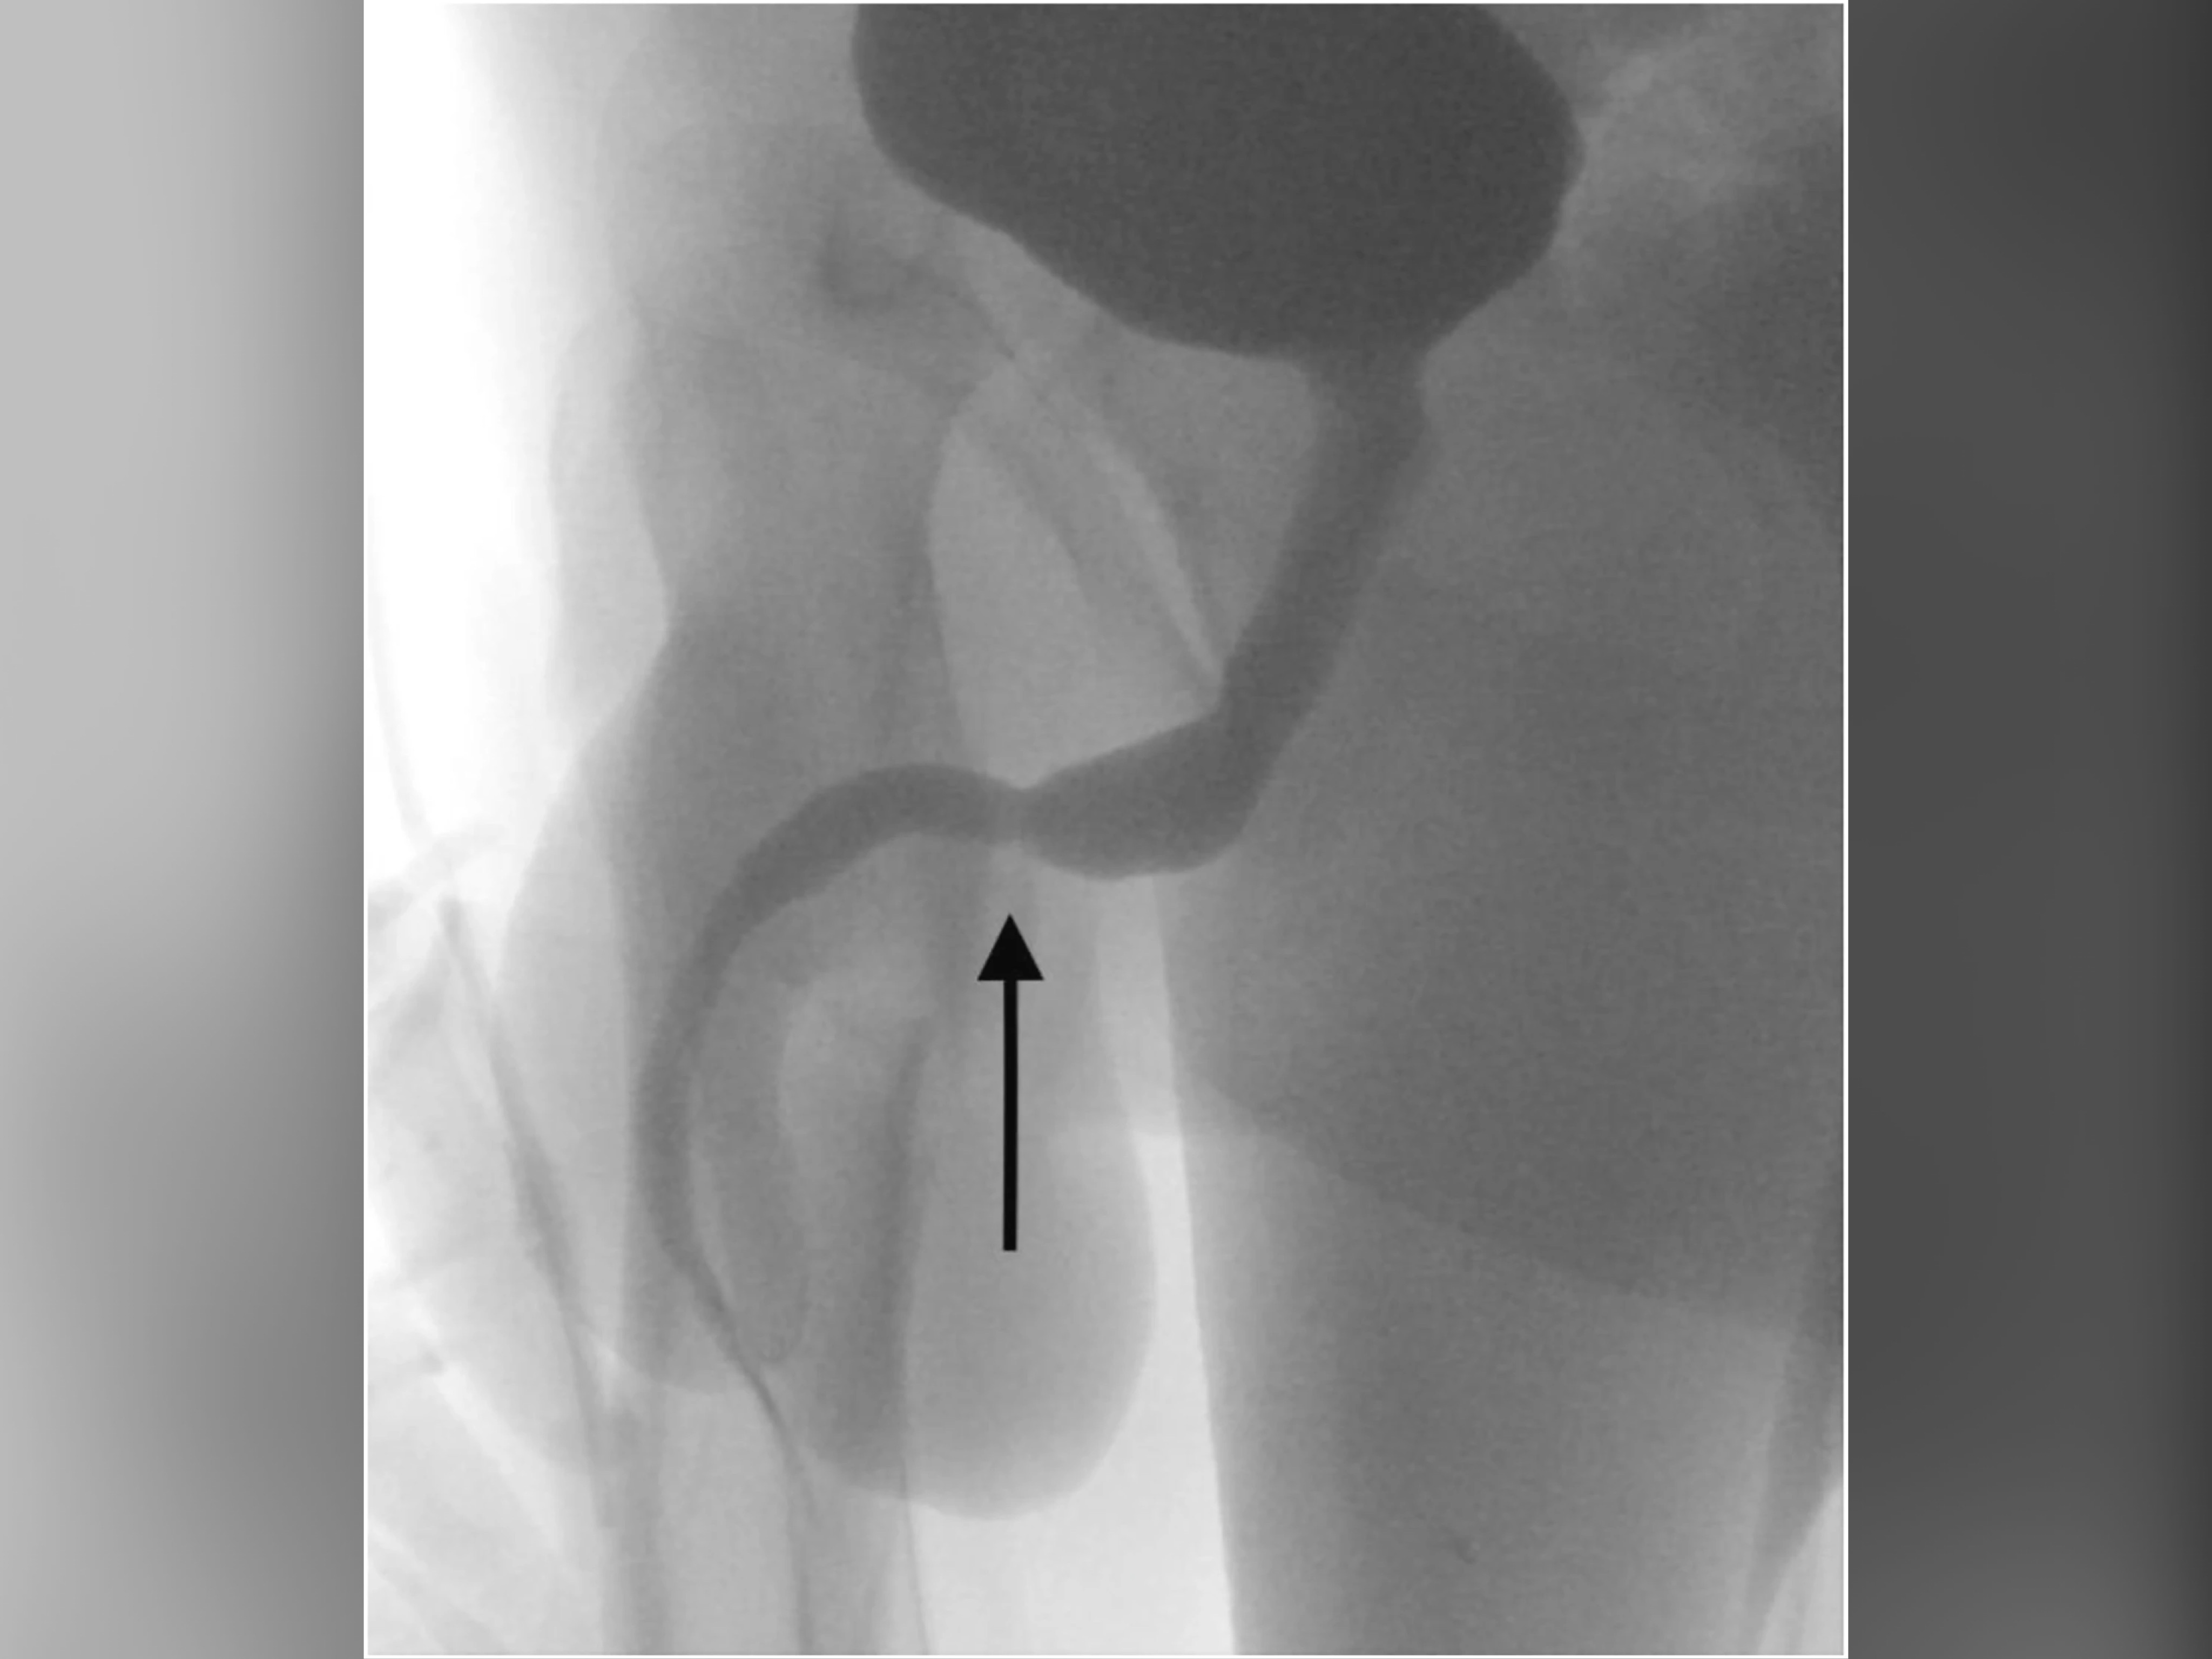

X-rays revealed that the veritable Gordian Knot of the USB cable in the urethra of the teenager.

Surgeons had to make an incision in between his genitals to get the bloody cable out.